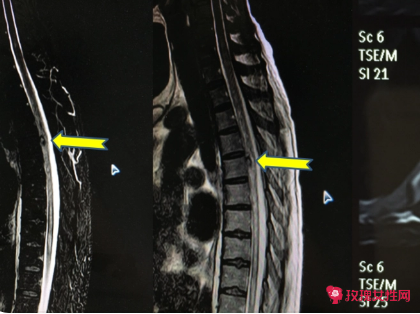

image.png